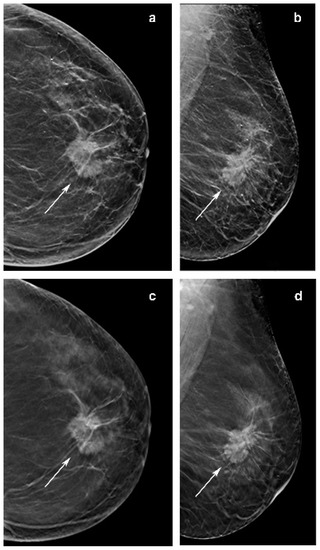

Figure 4.

Images of a 65-year-woman with a 38 mm, spiculated and palpable mass (arrow in a–d) in the upper central quadrant of the left breast detected at screening with digital breast tomosynthesis (DBT) plus synthetic mammography (synt2D). Mass was invasive lobular carcinoma. (c) Image from single-slice DBT in craniocaudal view. (d) Single-slice DBT image in mediolateral oblique view. (a) Image from synt2D in craniocaudal view. (b) Image in mediolateral oblique synt2D view. The mass is easily identifiable in synt2D and DBT, but DBT (c,d) increases the contrast, emphasizing the presence of spicules, and resulting in a better estimate of size.

As shown by the literature, our study confirmed that DBT could increase the conspicuity of ILC (Figure 3). In fact, 4/78 lesions were not recognized using only synt2D and were recovered by all breast dedicated readers only in DBT. Moreover, 18 to 27% of cases were recovered with DBT by at least one reader. Our data indicate that DBT increases detection of lobular breast cancer compared with synt2D: ILCs were more likely to have high conspicuity at DBT than at synt2D for each reader (Figure 5).

Other investigations reported that ILC is commonly presented as a mass on mammography. Of note, in our series 10/50 opacities were not recognized by at least one reader at synt2D but were visualized by all the readers at DBT. Two out of ten tumors with small diameter were identified in fatty breast only at DBT by all the readers (Figure 2). This could be explained by the better capabilities of DBT than synt2D in the evaluation of spiculated or ill-defined masses (Figure 3). Our results confirmed that calcifications with or without opacity due to their high density are easy to detect on both synt2D and DBT.